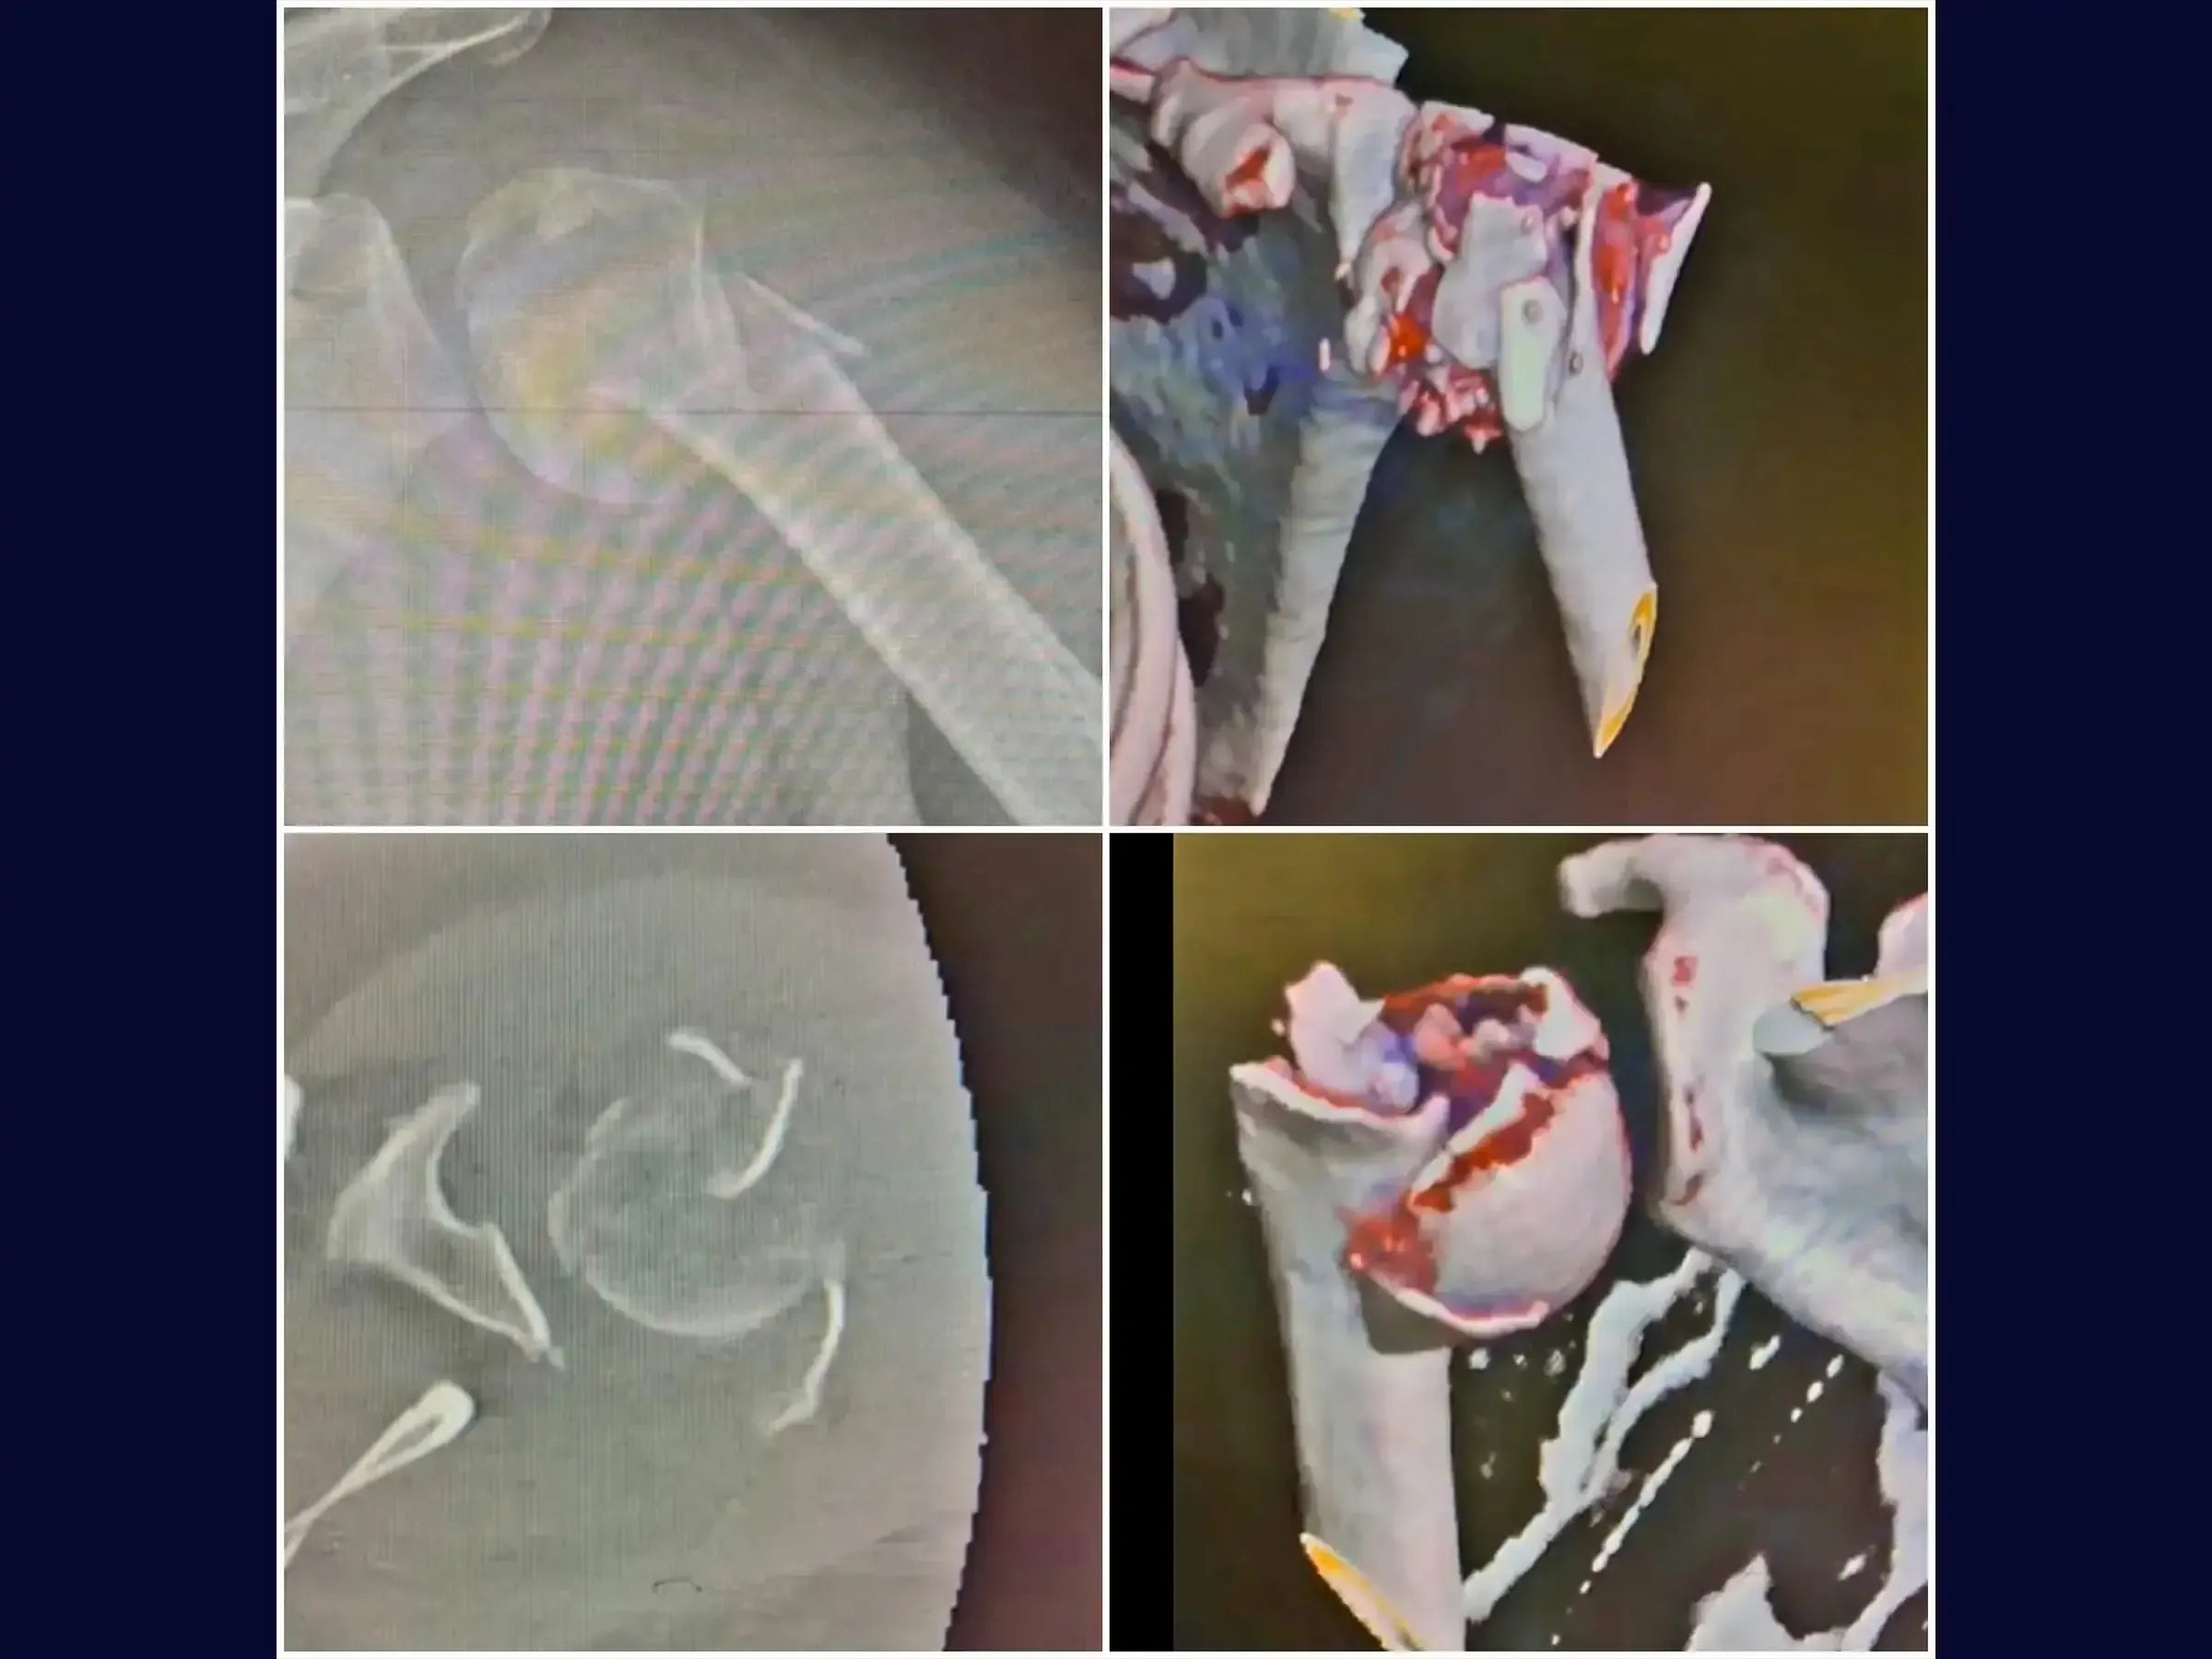

Domine o tratamento de fraturas complexas do úmero proximal. Este treinamento oferece uma imersão técnica na reconstrução de fraturas em quatro partes, com ênfase na abordagem deltopeitoral e fixação com placa e amarrilhas, apresentada em vídeo 4K sob a perspectiva do cirurgião.

- Reconstrução de fraturas complexas em quatro partes do úmero proximal.

- Redução de fragmentos e manobras de valgização.

- Reparo e Fixação de Tendões do Manguito Rotador: Protocolos para reparo do Subescapular, e técnicas para laçada, redução e fixação do Supraespinhal e Infraespinhal à placa, garantindo a estabilidade primária.

- Estratégias para Valgização da Cabeça Umeral: Abordagens para manipulação e valgização da cabeça umeral, incluindo o uso de fio de alta resistência e técnicas com broca e parafusos temporários para correção da impactação em varo.

- Tensionamento e Reforço das Amarrilhas: Metodologia para amarrilhas robustas com fios de alta resistência (FiberWire/FiberTape) nos tendões do manguito rotador, essenciais para a estabilidade rotacional e axial, com reavaliação e reaperto pós-valgização.